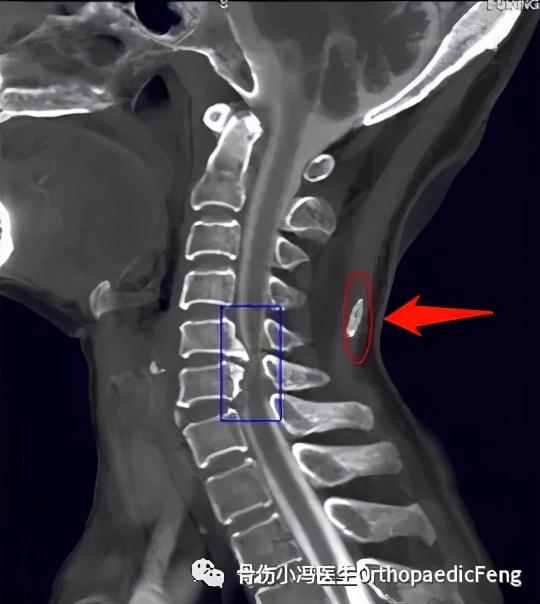

影像学上,项韧带常常可以见到钙化。颈椎前屈可能一定程度受限,但大多数患者不会出现疼痛。